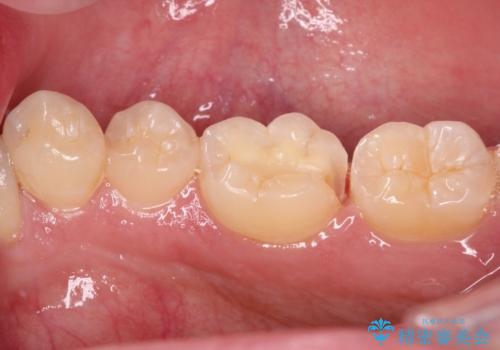

精度の高いセラミックインレーにて修復処置することとしました。

噛んだ時の痛みや、冷たいものがしみる症状はなくなり、見た目も自然でどこが詰め物かわからないと、患者様は大変満足されました。